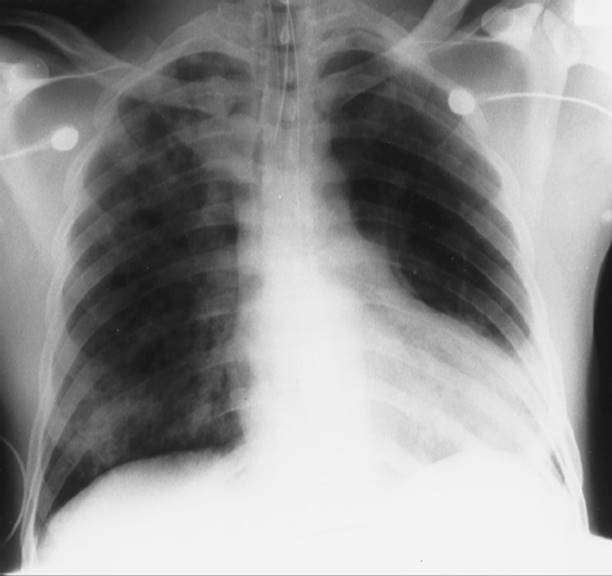

Ventilator-associated pneumonia (VAP), the most frequent type of nosocomial infection in the ICU, occurs in up to 30% of intubated patients.89 VAP consists of a pulmonary inflammatory reaction and sepsis in patients who are mechanically ventilated for a minimum of 48 hours. It is difficult to accurately diagnose, and because the underlying illness of critically ill patients often has a high mortality rate, it is difficult to differentiate to what extent mechanical ventilation contributes to the risk of nosocomial pneumonia.90 Historically, clinical findings have been used to diagnose pneumonia yet have not been shown to have sufficient accuracy, leading to the overuse of antimicrobial therapy (Table 19-7). Quantitative cultures are recommended to determine the bacterial load in a tracheal sample to differentiate colonization from infection and avoid overutilization of antibiotics. Clinicians may also see the use of biomarkers to assist in the diagnosis of VAP in the future.89

TABLE 19-7 Criteria for the Diagnosis of Pneumonia